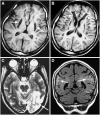

Because of their high-energy metabolism, neurons are strictly dependent on mitochondria, which generate cellular ATP through oxidative phosphorylation. The mitochondrial genome encodes for critical components of the oxidative phosphorylation pathway machinery, and therefore, mutations in mitochondrial DNA (mtDNA) cause energy production defects that frequently have severe neurological manifestations. Here, we review the principles of mitochondrial genetics and focus on prototypical mitochondrial diseases to illustrate how primary defects in mtDNA or secondary defects in mtDNA due to nuclear genome mutations can cause prominent neurological and multisystem features. In addition, we discuss the pathophysiological mechanisms underlying mitochondrial diseases, the cellular mechanisms that protect mitochondrial integrity, and the prospects for therapy.